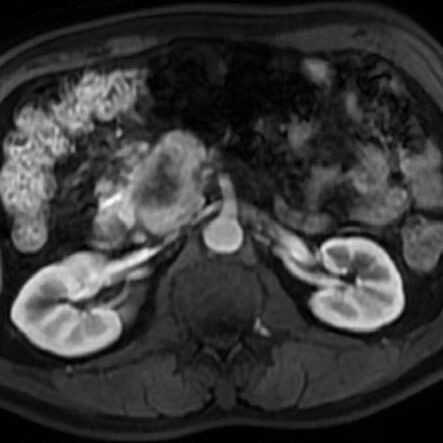

山穷水复,柳暗花明——以髓系肉瘤为首发表现的TTMV:RARA-APL一例